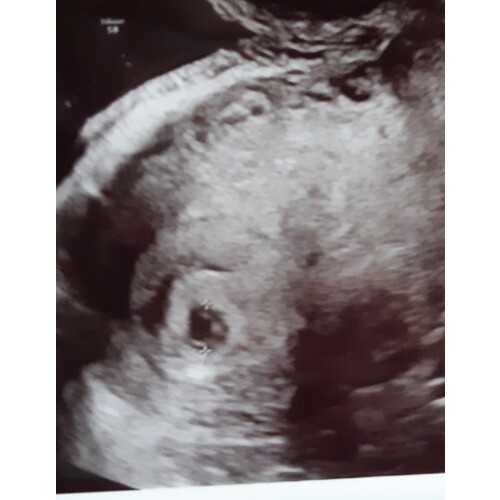

Hallo Fleuranna, ik heb precies hetzelfde. Ben eigenlijk 7.5 maar tijdens de eerste controle had ik een vruchtzakje dat wees op 4-5 weken. Ze zagen bij mij wel dooierzak en ik zie ( als het goed is) bij jou in het vruchtzakje ook iets kleins klopt dat? Zolang je geen pijn of bloed hebt mag je best nog positief blijven 鈽橈笍 wanneer mag je naar de controle? Ik mag morgen voor de 2de super spannend!

Dit was 5+5 kweet niet of je hier veel mee bent... Weet wel, als ze tellen vanaf je laatste menstruatie en je hebt een lange cyclus ben je 1week minder ver dan gedacht. En als je innesteling eerder tegen dag 12 ipv dag 7 was, scheelt het ook bijna een week. Ik ben zo van 7+2 naar 5+5 gezet